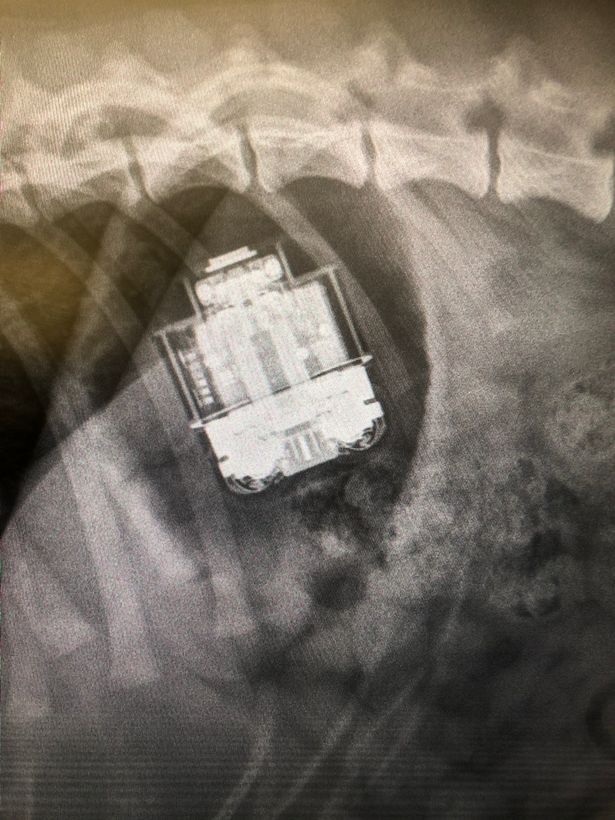

Susana Jauregui, the senior vet at the Hull-based practice, explained: "Our vet on duty that evening, Steven, X-rayed Jimmy and the radiograph images clearly showed the AirPods case still intact in his digestive system.

"There was a risk of it causing an obstruction and, with it being a charging case, Steven was also concerned about battery acid leaking so, after discussing the situation with Jimmy's owners, he agreed to operate.

To Steven's surprise, the case was completely intact - not a bite mark or scratch insight - and the charging light was still on.